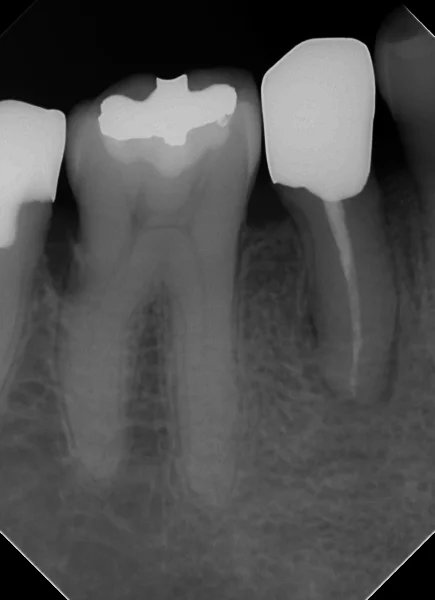

そして、1年半経過後、経過のレントゲンを撮らせて頂きました。

根の先の膿が随分と無くなってきているのが分かるかと思います。

それでもうっすら根の先の骨には空洞が残っていますね。

違和感や食事時の痛みなどは出ていませんので、特に問題はありませんが・・・

骨が完全に治るのには恐らくあと1年ほどは掛かりそうですね・・・。